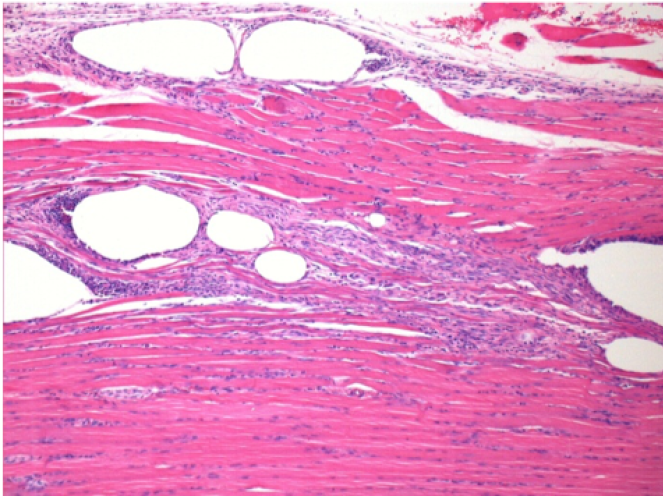

10 días después de la inyección de Endopeel 0,1 ml en el músculo pretibial derecho.

Aquí puede ver la formación de las vacuolas que están rodeadas de linfocitos. Las vacuolas son diferentes a la necrosis tisular. La presencia de linfocitos está relacionada con la permeabilidad de las membranas celulares.

07